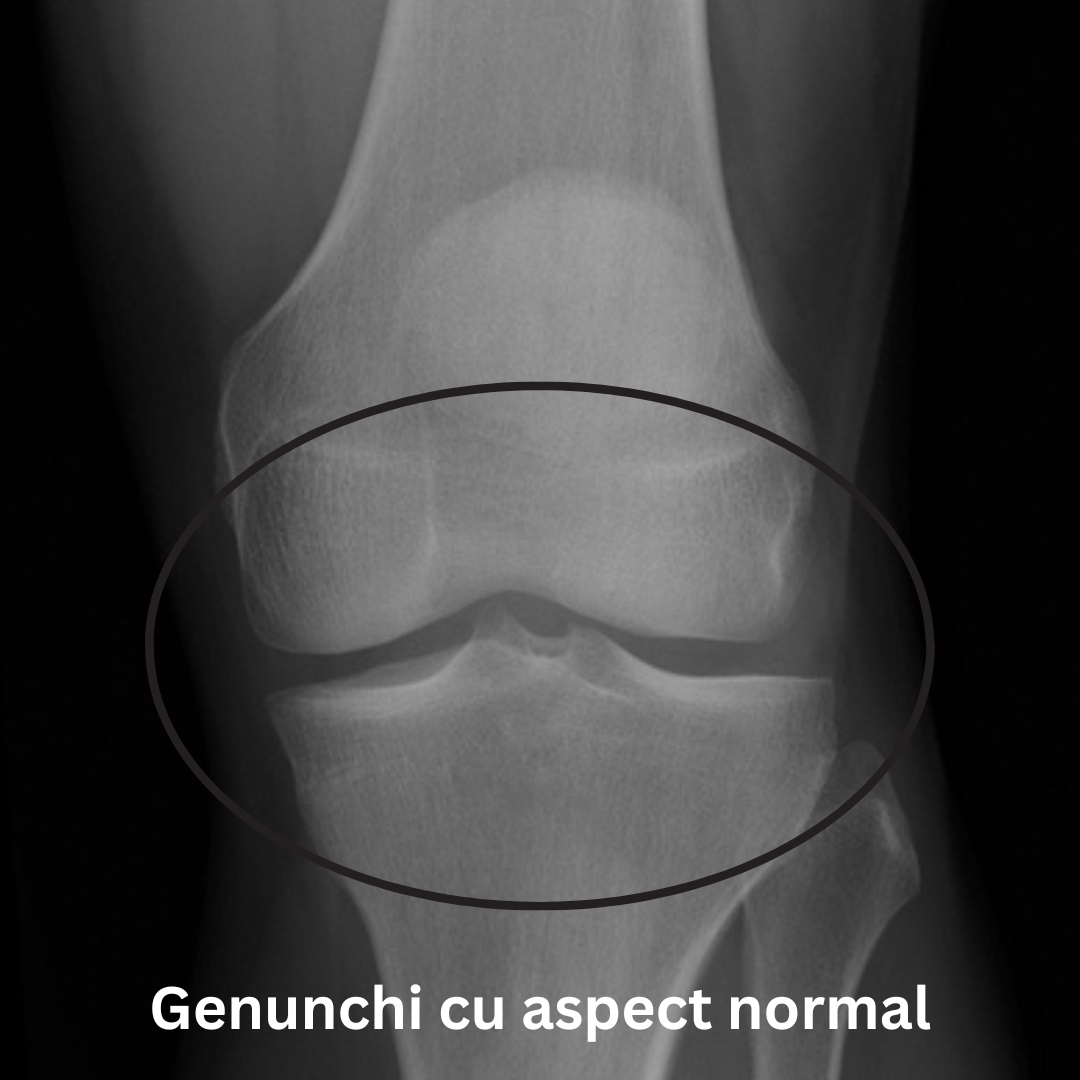

radiografie genunchiradiografie gonartroza

Radiografia unui genunchi artrozic poate arată o îngustare a spațiului articular, modificări ale osului, precum și formarea de osteofite (imaginea din dreapta).